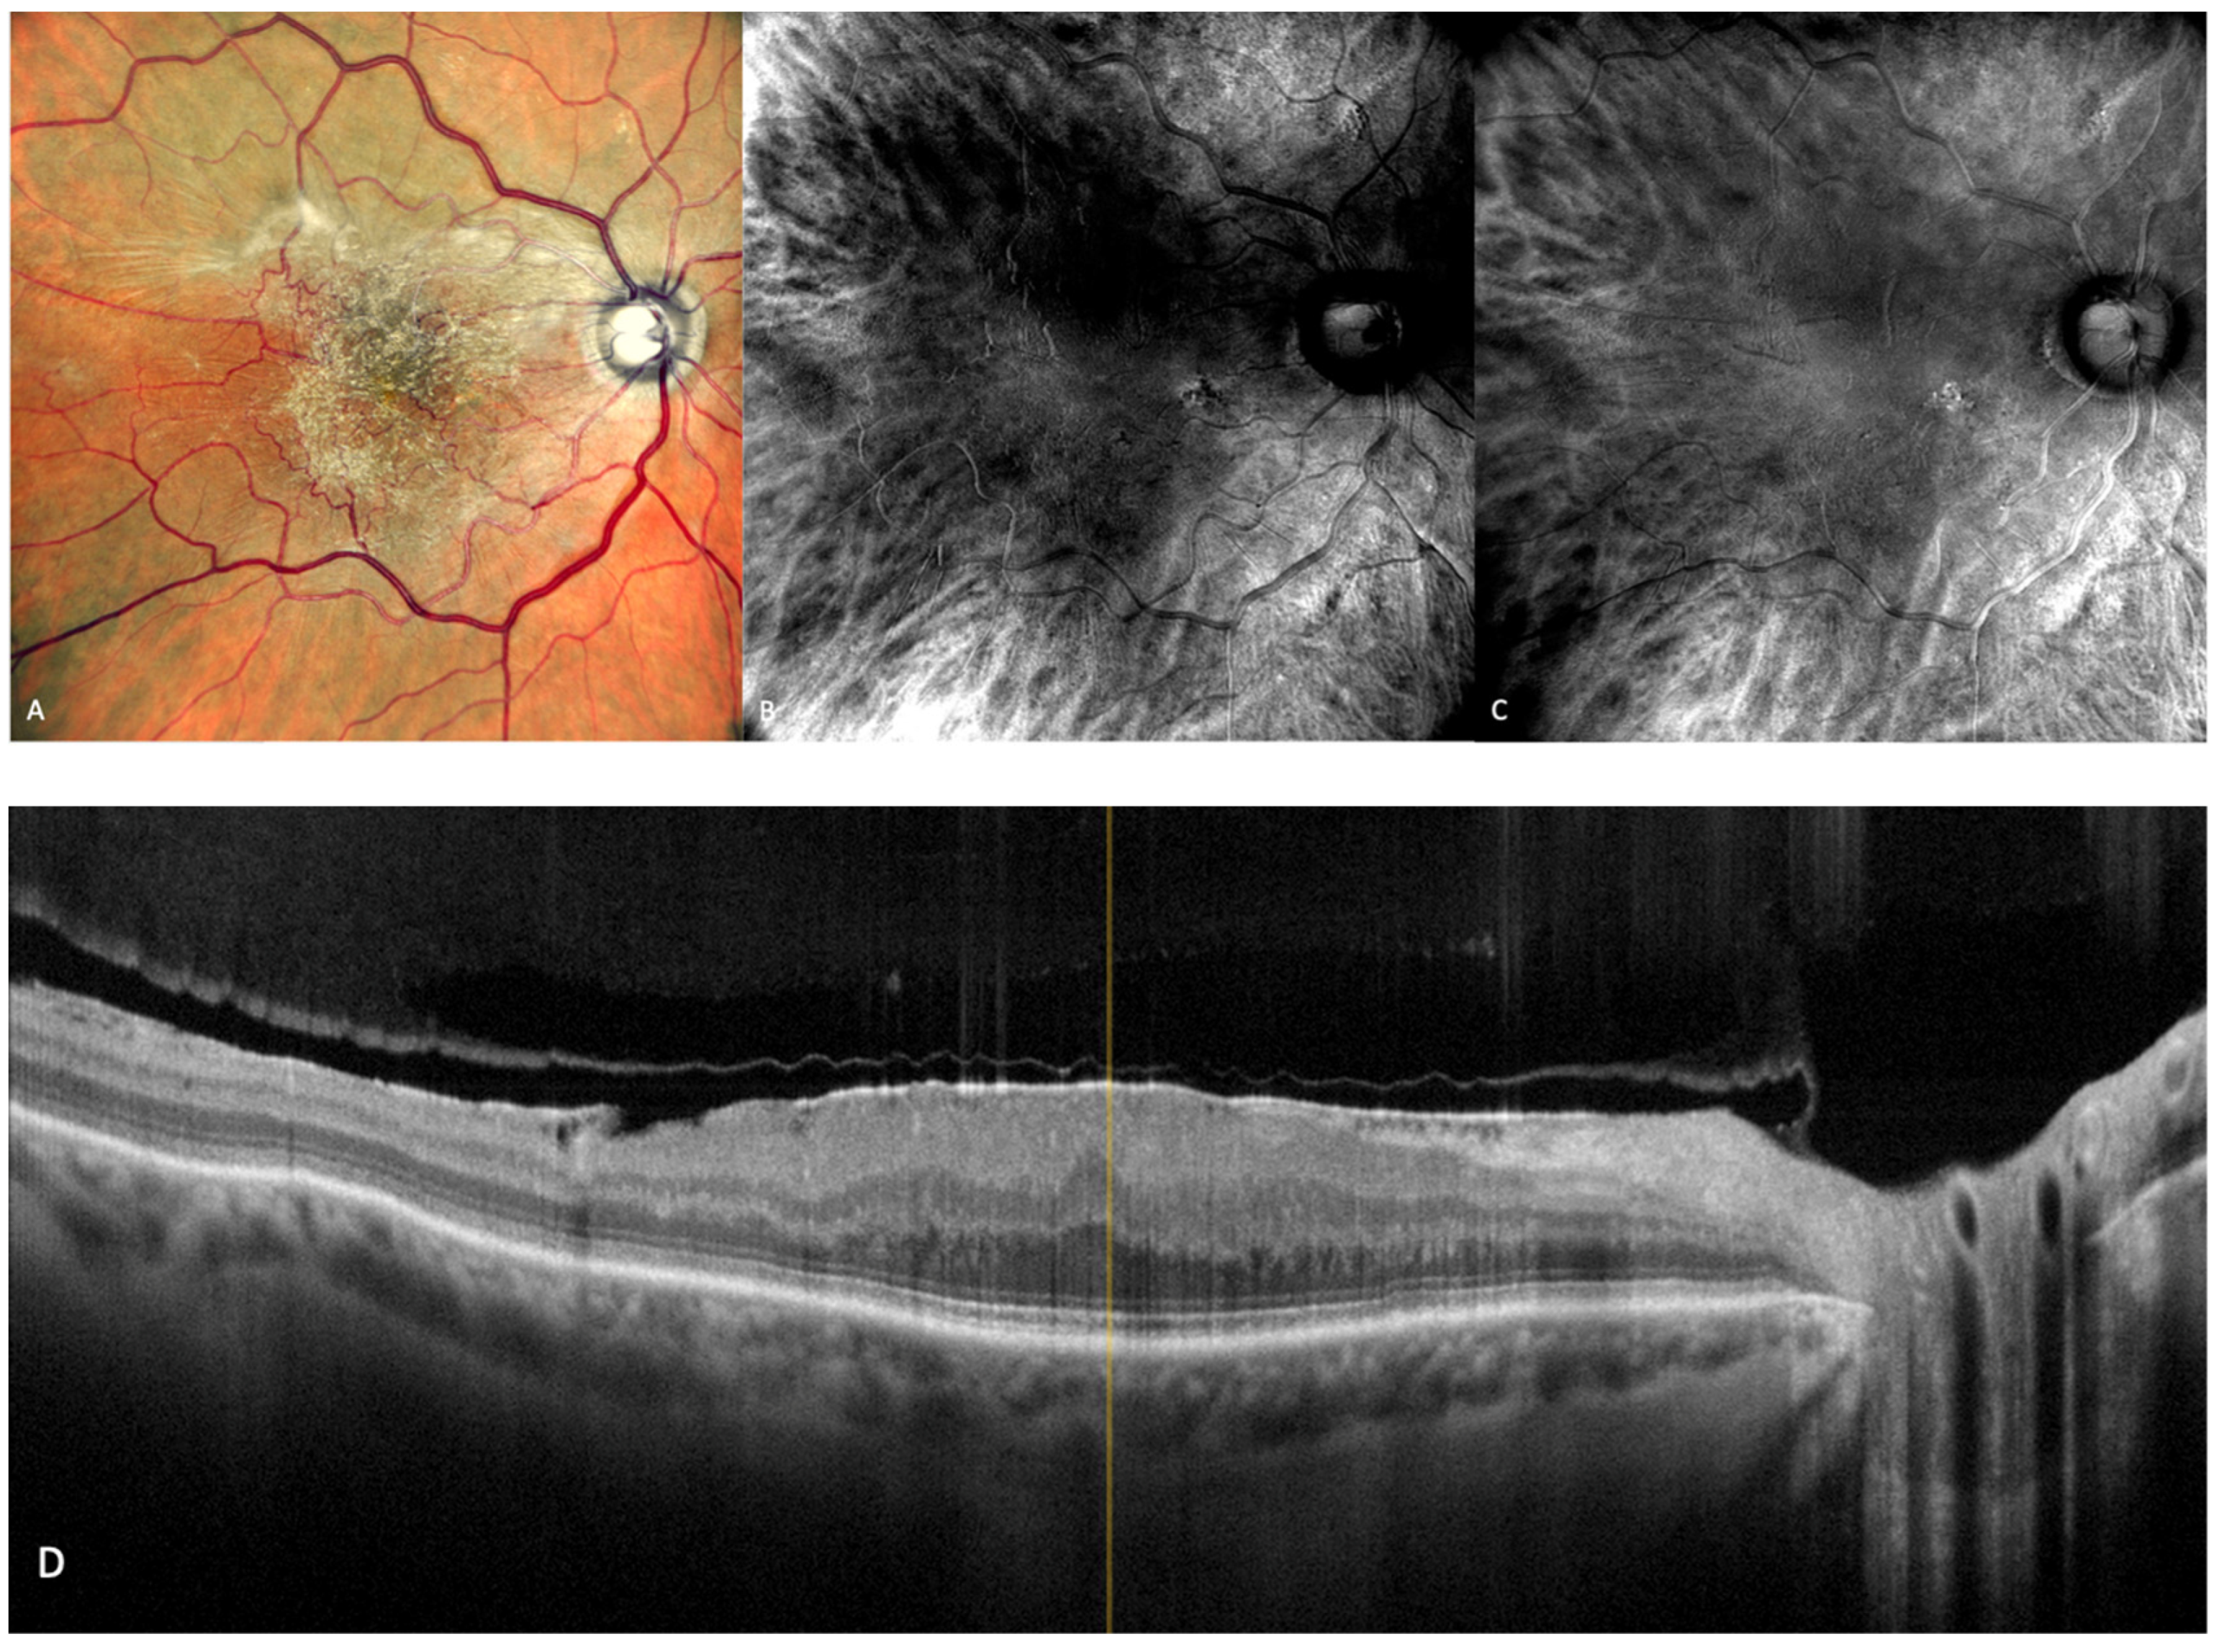

Figure 6.

Geographic atrophy. (A) cSLO image showing round patches of GA where the choroidal vessels are visible, surrounded by large and medium drusen. (B) Green FAF showing confluent hypo-autofluorescent areas. (C) DR and (D) DL retromode images of GA seen as round patches with homogenous reflectivity where the underlying choroidal vessels are visible. (E) SD-OCT showing RPE and outer retinal atrophy temporal to the fovea (red arrows) with foveal sparing (yellow short arrow). (F) SD-OCT showing large area of RPE and outer retinal atrophy (red arrows).

Retromode’s ability to detect and quantify GA was determined by Corradetti et al. by comparison to the classical methods with good and repeatable results [44]. The study compared multiple retinal imaging modalities: retromode deviated-right (DR), retromode deviated-left (DL), confocal color fundus photography (cCPF), and green and blue fundus autofluorescence (G-FAF and B-FAF) using a scanning laser ophthalmoscope [44]. The study revealed the following results using cCFP, G-FAF, B-FAF, retromode DR, and retromode DL, respectively: the mean area of GA was measured as 9.76 mm2, 9.75 mm2, 9.76 mm2, 9.82 mm2, and 9.81 mm2. Even though there was a numeric difference, and the area measured with retromode DR and DL is larger, the difference is not statistically significant and may be due to a greater sensitivity of the method to detect atrophic changes [44].

The aspect of GA on a retromode illumination image is represented by a pseudo3D round patch with a homogeneous reflectivity and clearly visible hyperreflective choroidal vessels seen under the retina (Figure 6C,D) [44].